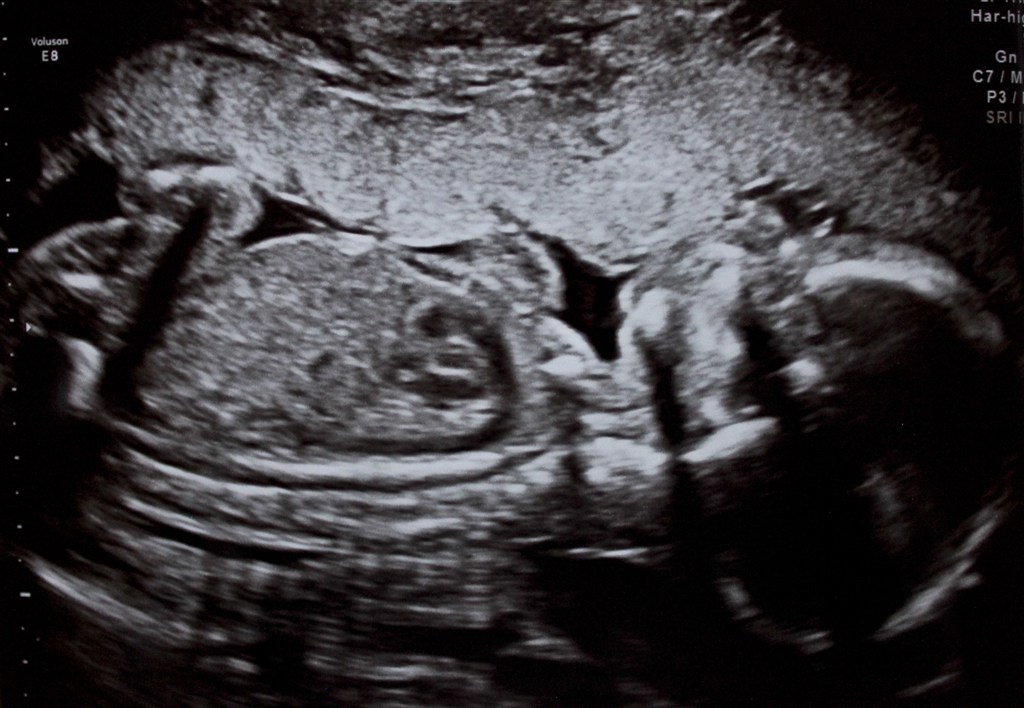

Billede nr. 1: Hun ligger og kysser moderkagen (som i øvrigt ligger udad, så det er nok derfor, jeg ikke mærker hende så meget endnu).

Hun så fuldstændigt fin ud, der var intet at komme efter og hun tager på, som hun skal, hvilket beroligede mig meget! Hun vejer 300 gram og hendes hjerte er på størrelse med en lillefingernegl... Awww